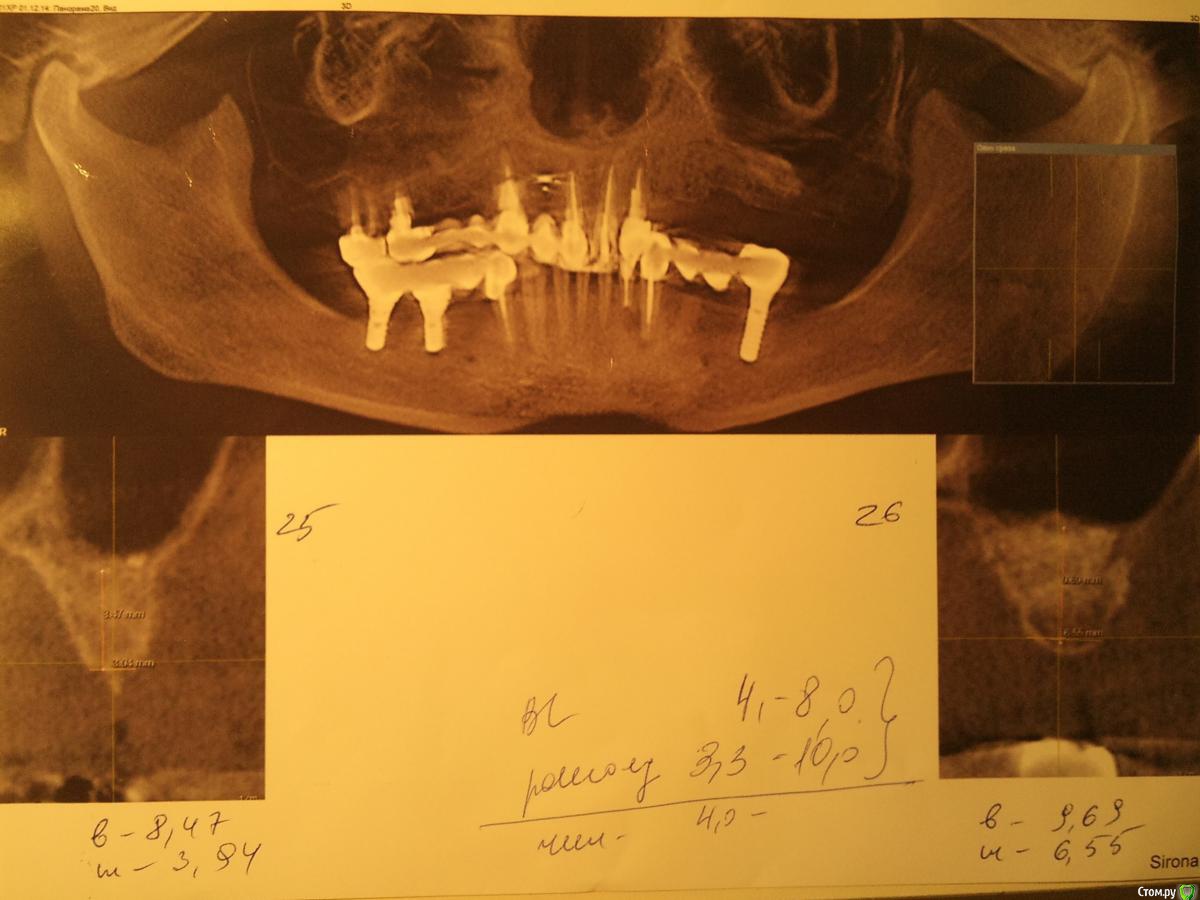

Елена62 Опубликовано 4 января, 2015 Поделиться Опубликовано 4 января, 2015 Женщина, 52 года.Кратко: нижняя челюсть приемлемая.На верхней: слева 8 мес назад был сделан синус лифтинг для предстоящей имплантации (операция назначена через 2 недели), справа был мост на коронках (1-3-6). 3 и 6 под коронками сгнили, надо удалять. Мост сегодня слетел. На верхней челюсти фактически остались два передних депульпированных обточенных зуба. По-хорошему надо делать синус лифтинг справа, ждать мин 6 мес, ставить импланты, ждать приживления, ставить мост. Но пока и слева еще импланты не поставлены, не говоря о мосте на них.Дайте, пожалуйста, совет: Какие варианты решений можно рассмотреть, чтобы с одной стороны иметь возможность жевать, с другой -провести корректные имплантации? Ссылка на комментарий

Bier Опубликовано 7 января, 2015 Поделиться Опубликовано 7 января, 2015 не поняли, удалить все зубы, поставить имплантаты и сделать синуслифтинг справа в одну операцию. Имплантатов надо 7-8 шт.Часть имплантатов нагрузить сразу, часть после приживления. 1 Ссылка на комментарий